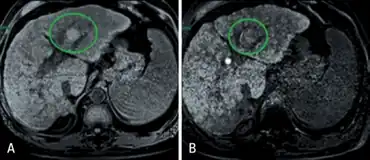

| a,b) MRI with liver-specific contrast in chronic liver disease individual | |